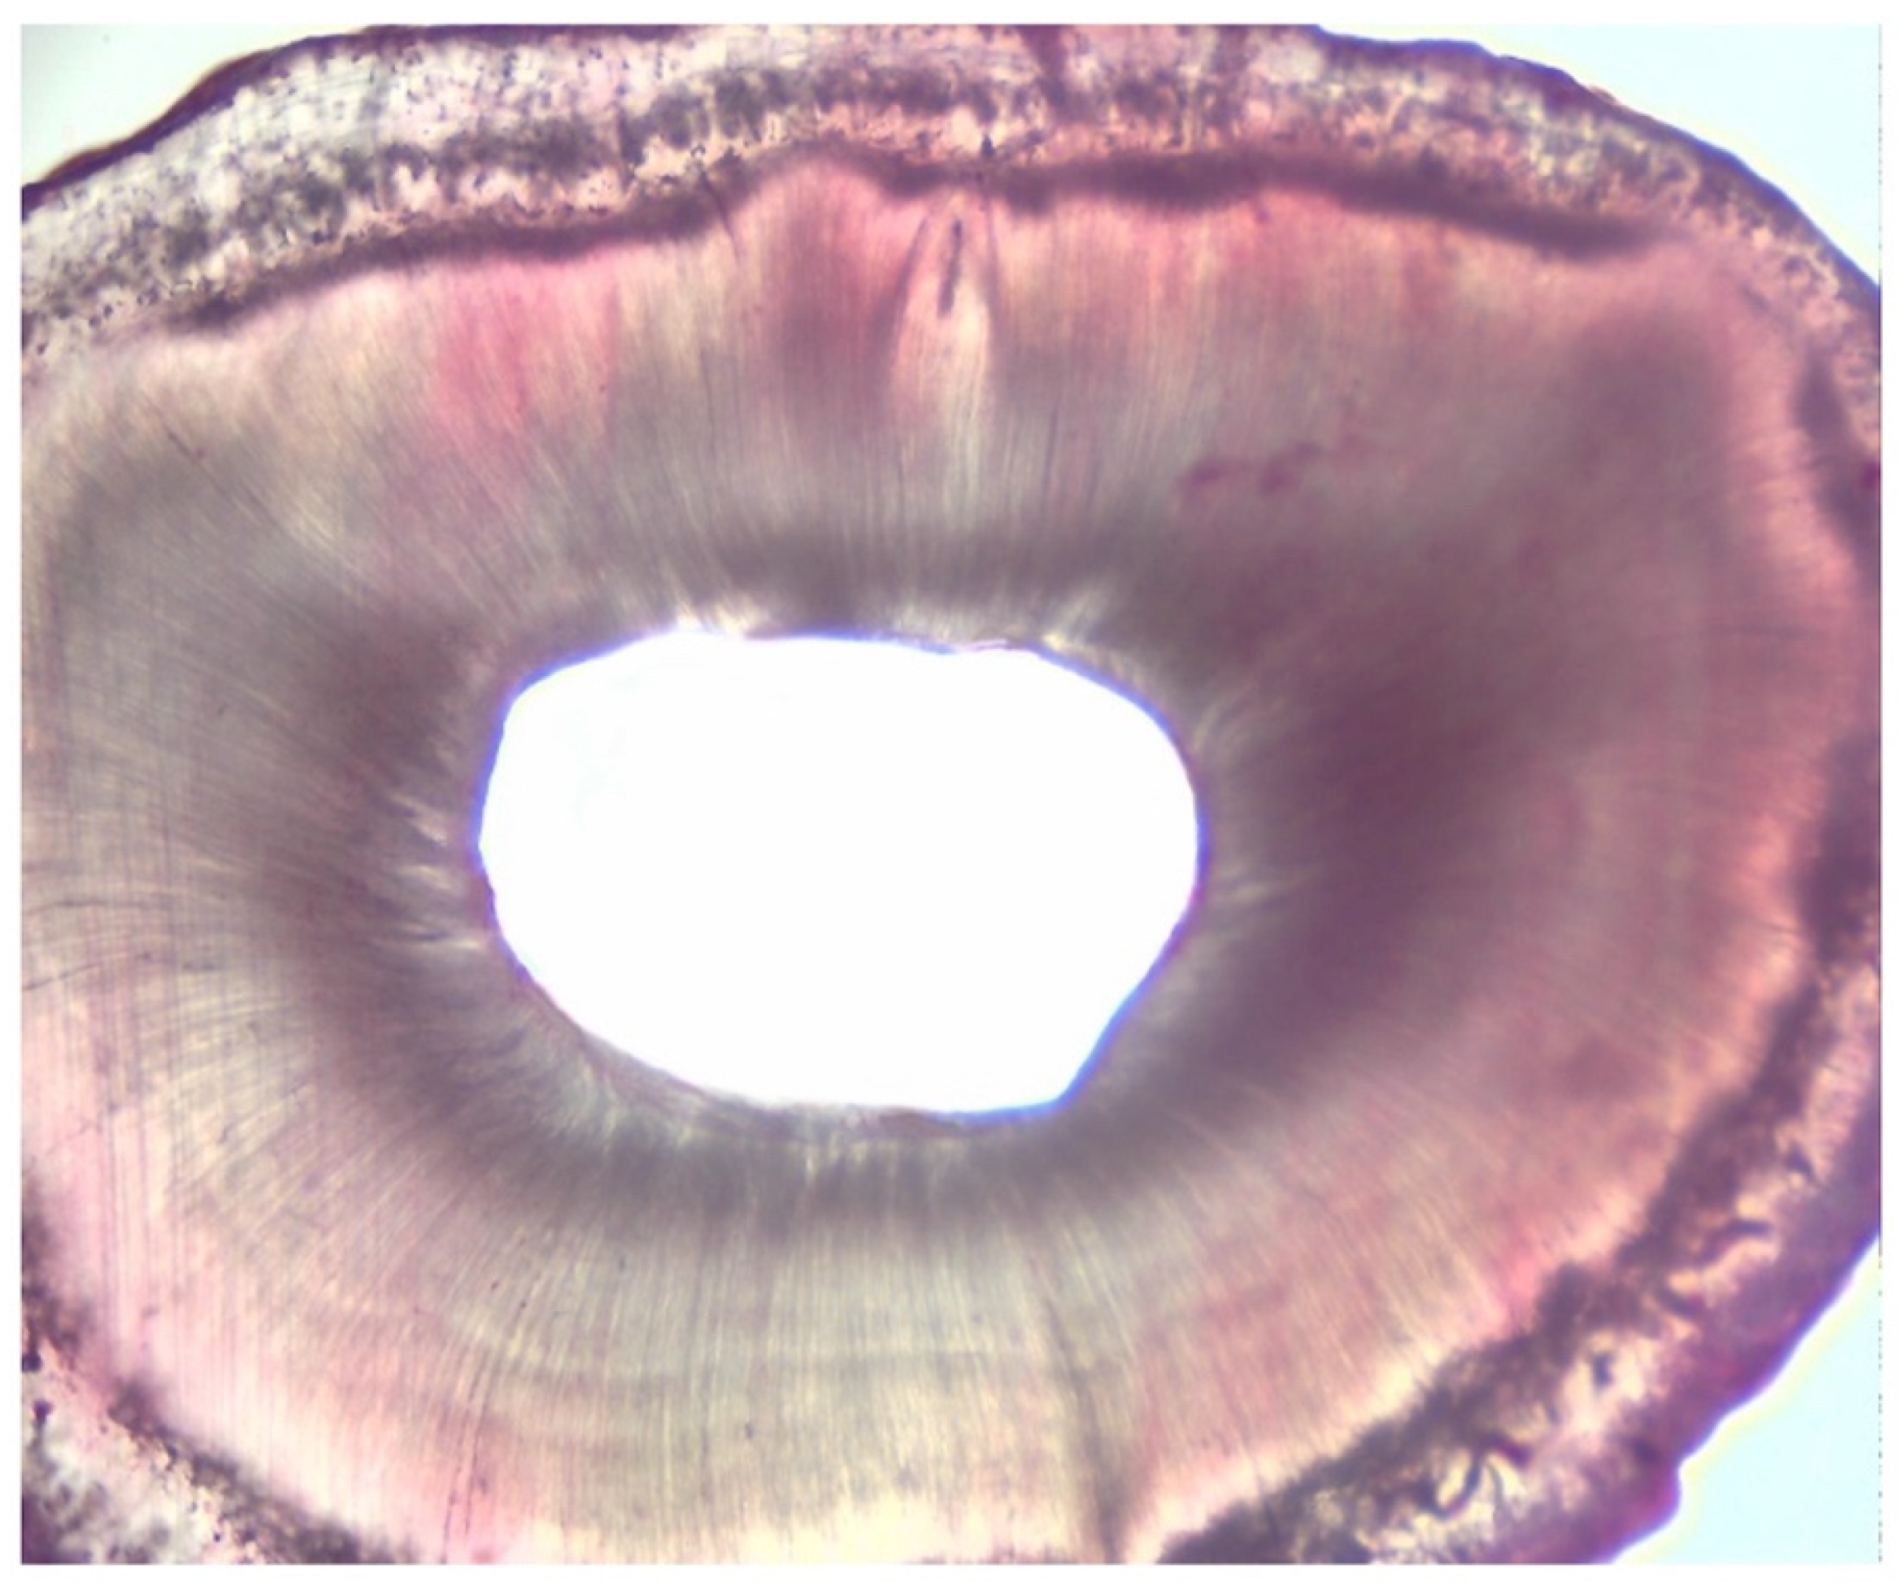

2.3. Assessment of Root Canal Cleanliness

| Grading | |

|---|---|

| I | presence of debris within the area |

| II | presence of debris in more than 50% of the entire area |

| III | presence of debris in more than 25% of the entire area |

| IV | absence of debris or presence of debris in less than 25% of the entire area |

| Group 1 | 2 [0.5] A |

| Group 2 | 4 [1] B |

| Score | I | II | II | I | II | III | II | II | II | I | II | I | II | III | II | II | III | II | I | II |

| Score | III | IV | IV | III | IV | III | III | IV | III | IV | IV | III | IV | IV | III | III | IV | IV | IV | IV |